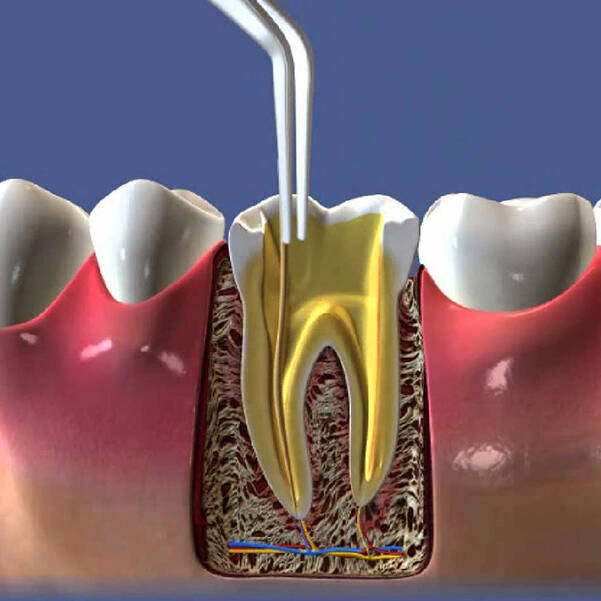

A Endodontia foca no tratamento da polpa dentária (o nervo do dente), que pode ser acometida por infecções, inflamações ou até necrose. Quando o tecido da polpa está comprometido, o tratamento de canal é necessário para salvar o dente e evitar complicações maiores. O procedimento consiste em remover o tecido danificado, limpar e desinfetar o canal radicular e, por fim, preencher o espaço com materiais biocompatíveis que garantem a recuperação e funcionalidade do dente.

- Remoção da Polpa: Quando o nervo está danificado (inflamado, infectado ou morto), ele é removido do interior do dente.

- Limpeza e Desinfecção: O canal radicular é cuidadosamente limpo e desinfetado para remover qualquer resquício de tecido infectado.

- Preenchimento do Canal: Após a limpeza, o canal é preenchido com um material específico que evita novas infecções.